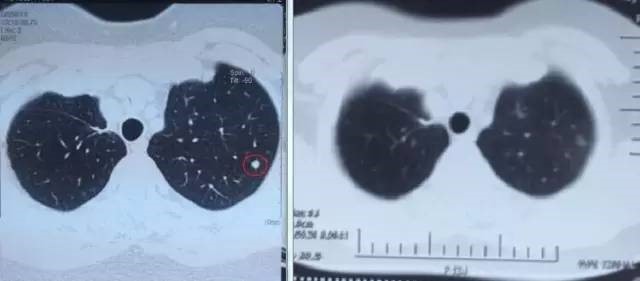

左图红色圈内是A45治疗前三个肺癌病灶,右图为治疗后病灶消失

患者一年多来一直听到的都是坏消息,治疗做完后回家了,也是不放心,直到9月6日复查结果出来,肺上三个病灶消退,一年多来终于等来一个好消息,开心的不要不要的,笑容重新回到了她的脸上,先生说,现在太太每天在家开心的逗孙子玩,自己感觉体力充沛了许多,每天可以走七八千步锻炼。苏州大学附属肿瘤医院专家建议说,患者现在暂时不需要治疗了,三个月后再进行一次A45巩固治疗,增强免疫即可 。